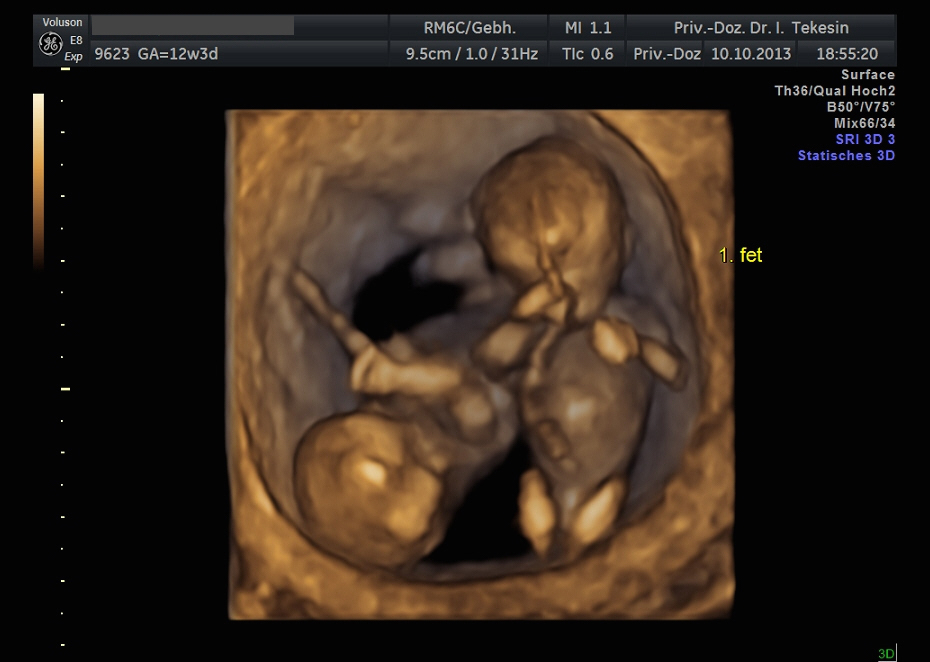

Kind in der 12. Woche (3D-Darstellung)